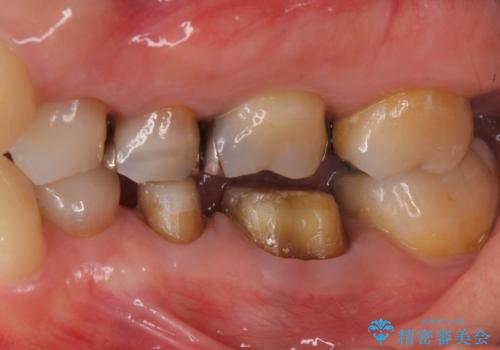

下の銀歯をセラミックに 虫歯治療

- 左下の銀歯を白くしたいと来院。

左下5番は根管治療のやりなおし、左下6番は上物(クラウン)のやり替えのみを行いました。

左下7番はアマルガムが入っていたため、ご希望によりセラミックインレーで治療を行っています。

- 44万円(内訳 左下7:emaxプレスインレー 左下6:仮歯、ジルコニアクラウン 左下5:精密根管治療再治療、ファイバーコア、仮歯、ジルコニアクラウン)費用は治療当時の料金となります